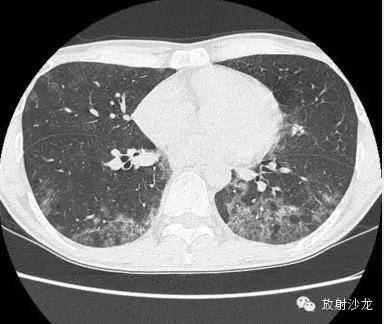

两周后的CT和X线:

胸片示两肺中下野边界不清的磨玻璃样阴影(GGO)。CT示两肺地图样分布的GGO,主要位于两肺上叶、右肺中叶及两肺下叶,其中两肺下叶多发的GGO融合并伴有小叶间隔增厚。2周后随访胸片示双肺野弥漫分布的GGO增多。患者第一次就诊时未告知自己的性取向。只告知了曾接触过染发剂。患者按肺间质性疾病给予激素治疗。然而,治疗后患者的症状和影像学表现均加重。患者血液检测结果显示艾滋病病毒阳性。支气管肺泡灌洗液GMS染色示大量的卡氏肺孢子虫。